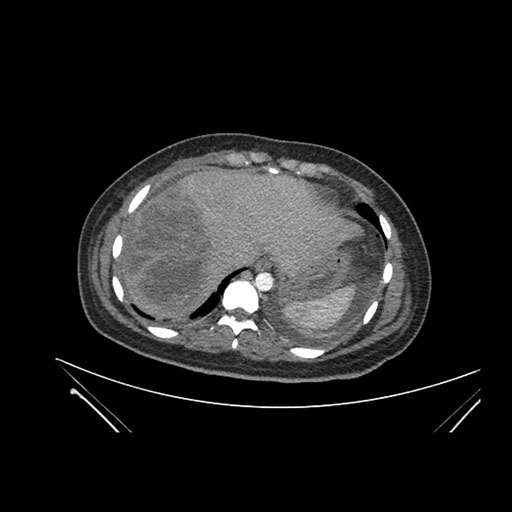

Axial Arterial

Axial Venous